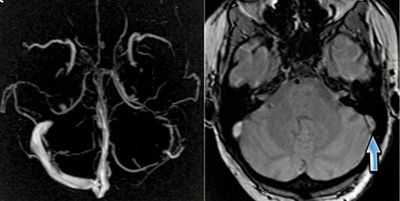

, sinus durae matris. Венозные каналы с неспадающимися стенками между листками твердой оболочки головного мозга. Собирают кровь от мозга, его оболочек и отводят ее во внутреннюю яремную вену. Рис. Б, Рис. В.

Поперечный синус

, sinus transversus. Начинается от синусного стока и продолжается латерально в сигмовидный синус. Рис. Б, Рис. В.

Синусный сток

, confluens sinum. Расположен у внутреннего затылочного выступа. Является местом, где сходятся верхний сагиттальный, прямой, затылочный и поперечный синусы. Рис. Б, Рис. В.

Сигмовидный синус

, sinus sigmoideus. Продолжение поперечного синуса кпереди. Образует S-образный изгиб перед яремным отверстием и переходит в bulbus superior venae jugularis. Рис. Б, Рис. В.

Нижний каменистый синус

, sinus petrosus inferior. Проходит от пещеристого синуса к яремному отверстию вдоль заднего края пирамиды височной кости. Рис. Б.

Верхний каменистый синус

, sinus petrosus superior. Проходит от пещеристого к сигмовидному синусу вдоль верхнего края пирамиды височной кости. Рис. Б.